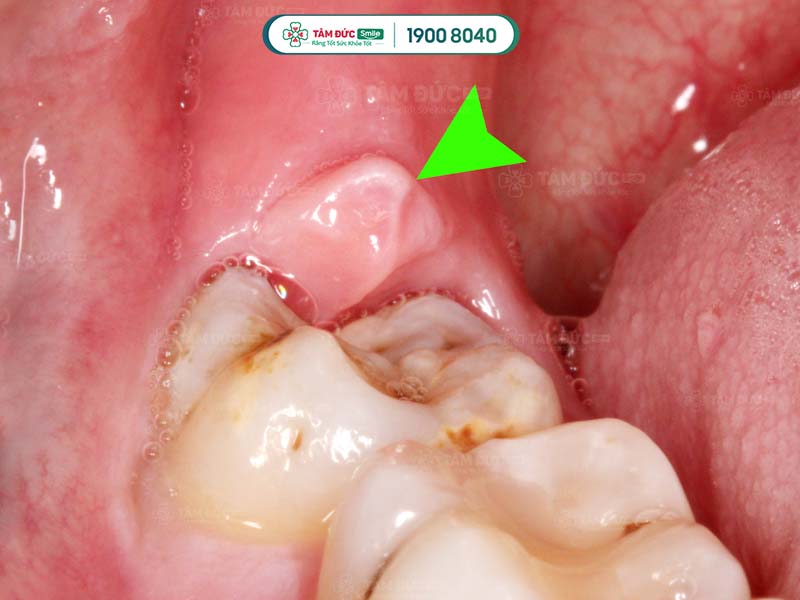

Viêm sưng nướu răng trong cùng

Bên cạnh đó, viêm lợi trùm cũng là nguyên nhân dẫn tới sưng nướu răng. Bị sưng nướu răng trong cùng hàm dưới do viêm lợi trùm thường đi kèm với hiện tượng chảy mủ và hôi miệng.

Viêm lợi răng khôn

2.3. Răng khôn mọc lệch

Răng khôn sẽ mọc khi Quý khách ở tuổi trưởng thành. Vì là răng mọc sau cùng nên dễ xuất hiện tình trạng mọc lệch, hay mọc đâm vào răng số 7… Khi mọc răng khôn, vùng nướu trong cùng xuất hiện tình trạng sưng viêm và đau nhức.

Răng khôn mọc lệch làm sưng nướu răng